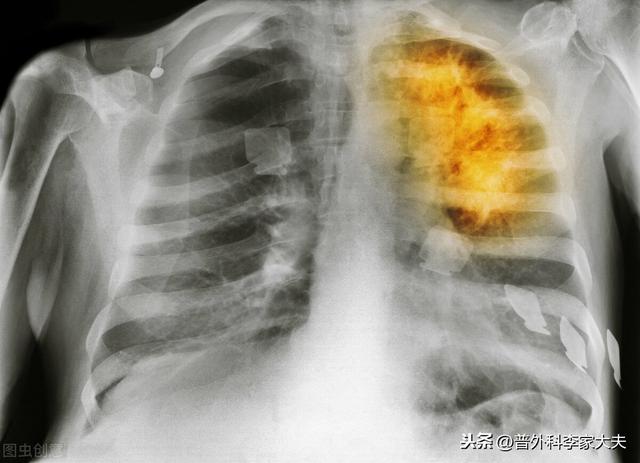

毎年80万人近くの肺がんの新規患者が発生しており、患者の約85%は非小細胞肺がんで、小細胞肺がんとは異なり、悪性度が低く、ステージI、II、IIIAの患者のほとんどは手術が可能で、手術も最も直接的で効果的な治療法である。小細胞肺がんも手術が可能ですが、手術が可能なのはごく初期の初期症例だけです。手術後の肺がんの治療法は?

肺がんは、長期にわたる発がん因子が体に作用した後に発生するため、肺がんが発生すると、肺組織内の他の細胞も肺がんの発がん因子の影響を受け、肺がん病変の過程で病変細胞となる。肺がんが発見され、手術が行われたばかりでは、肺がんの腫瘤を取り除くだけで、他の肺病変細胞を取り除くことはできない。このため、肺がん患者は何期であっても、手術後に発がん因子が除去されない限り、肺がんの再発を繰り返すことになるのです。

また、小細胞肺がんは、受診時の90%以上がすでに胸腔内転移や遠隔転移を有しているため、外科的治療は基本的に勧められない。したがって、肺癌が発見され手術を行う場合は、基本的に非小細胞肺癌患者であるべきである。したがって、肺がんが発見され手術を行った後、肺がんの病期が異なる患者さんでは、上記の肺がんの病期に関係なく行うべきこと以外に、今後行うべきことはやはり異なります:

0期や1期の早期非小細胞肺がんの患者さんが、肺がんの真の根治切除である手術を受けた場合、術後補助化学療法やその他の標的療法は必要ありません。手術後に患者さんがしなければならないことは、肺がんの再発を防ぐことです。上記のように肺がんの発がん因子を取り除き、肺がんの定期的な経過観察・見直しがしっかり行われていれば、一般的には、この種の患者さんは術後半年に1回、2年以降は1年に1回、全身の検査を受けた方が安心です。